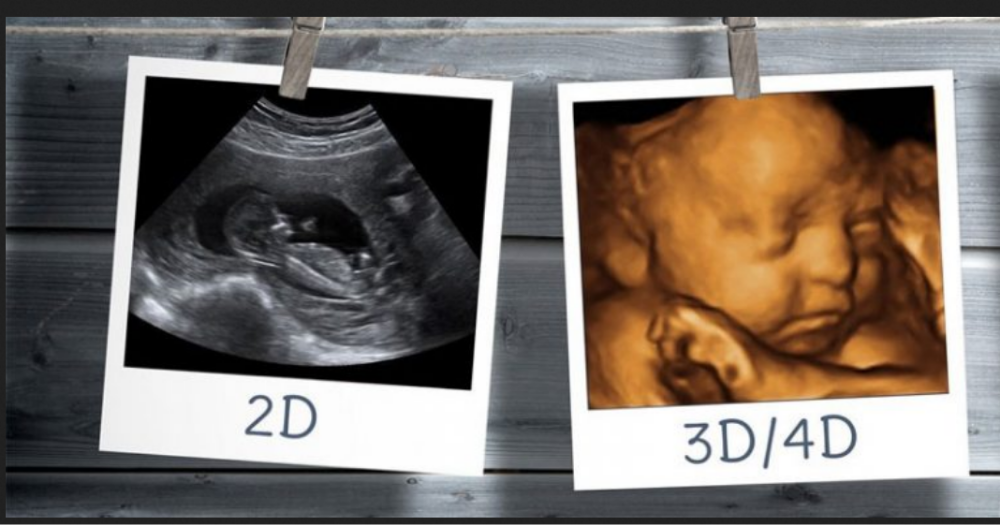

गर्भावस्था के दौरान ultrasound करवाना एक बेहद जरूरी test है, ताकि बच्चे की ग्रोथ, विकास और स्वास्थ्य का सही-अनुमान लगाया जा सके। आजकल traditional 2D ultrasound के साथ-साथ 3D और 4D ultrasound भी काफी लोकप्रिय हो गए हैं, क्योंकि यह बच्चे की अधिक स्पष्ट, realistic और moving images प्रदान करते हैं। बहुत से माता-पिता खासतौर पर 3D/4D scan करवाते हैं ताकि वे अपने होने वाले बच्चे का चेहरा, मुस्कान, हाथ-पैर और हर प्यारी activity पहली बार करीब से देख सकें।

3D ultrasound तकनीक पारंपरिक 2D ultrasound से अलग है क्योंकि इसमें बच्चे की तीन-dimensional (3D) image दिखाई देती है। इस scan में baby के चेहरे की बनावट, नाक, आंखें, होंठ, हाथ-पैर और skin surface features बहुत स्पष्ट दिखाई देते हैं। इस कारण parents को पहली बार बच्चे का चेहरा देखने का एक खास अनुभव मिलता है।

4D ultrasound, 3D का advanced version है। इसमें आपको baby की moving images (real-time video) दिखाई देती हैं। यानी बच्चे की हर activity — जैसे मुस्कुराना, जम्हाई लेना, हाथ-पैर हिलाना — live दिखाई देती है। यही वजह है कि 4D scan अधिक emotional और bonding experience देता है।

3D और 4D दोनों scans pregnancy imaging को अधिक clear बनाते हैं। फर्क सिर्फ इतना है कि 3D में आपको still 3-dimensional images मिलती हैं लेकिन 4D में real-time video मिलती है।

3D – Still image

4D – Moving video